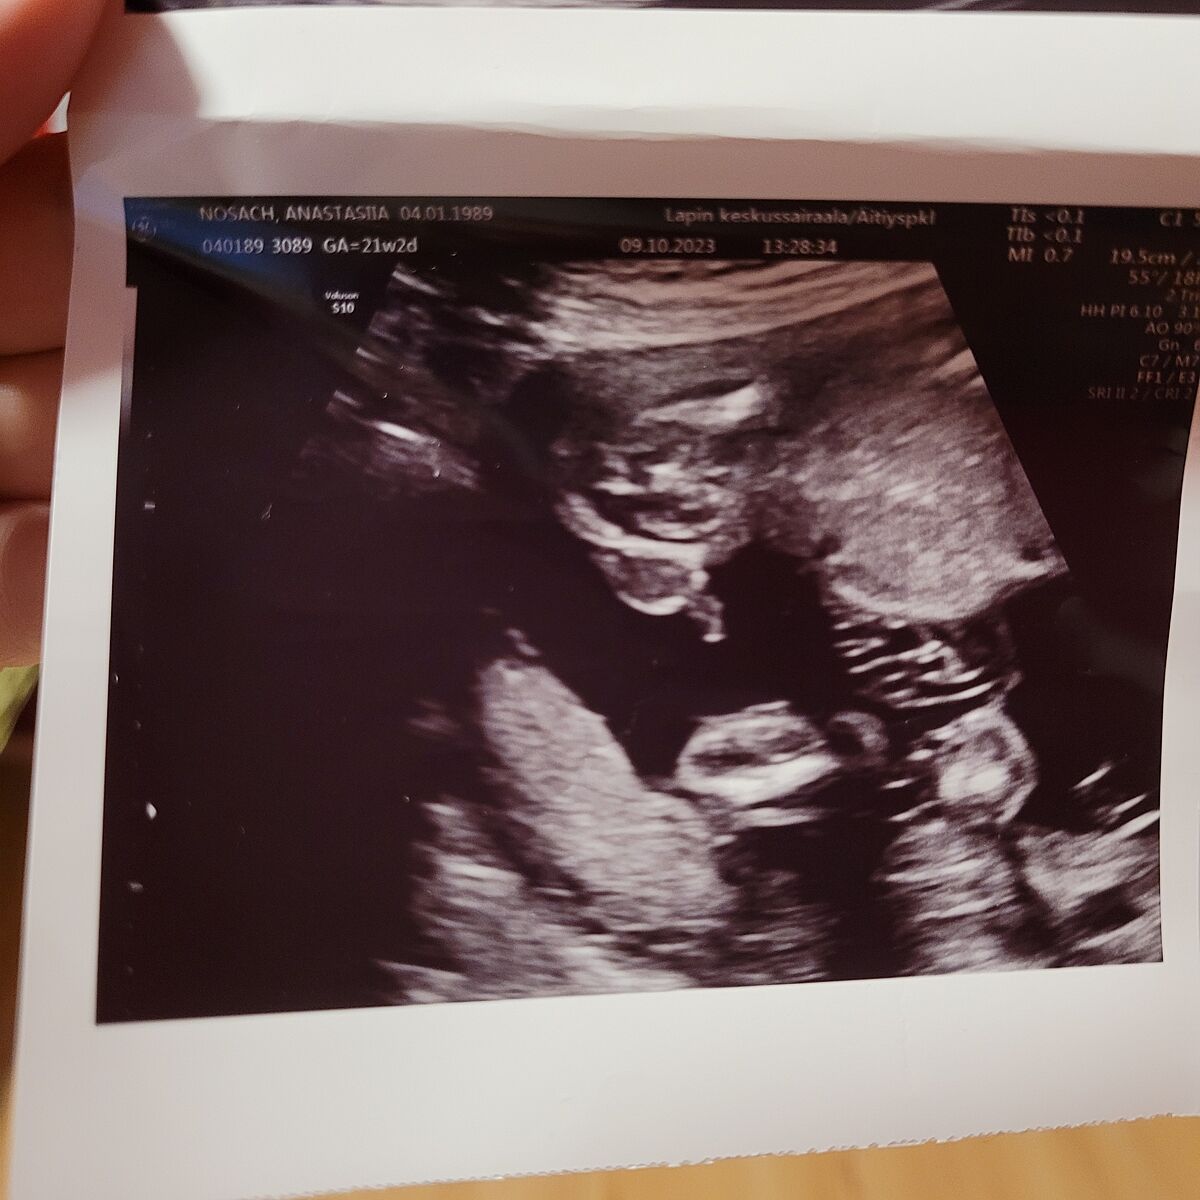

Мне врач только такие фото давала

Таке теж є) але на 15 тижні і там взагалі не видно що між ніжками))

автор, я нічого там не розумію, але в 15 тижнів не уявляю, як лікар може не зрозуміти стать дитини. Мені обидва рази ще в 10 тижнів визначали.

Ось такі лікарі закордоном) мій австрійський лікар сказав хлопчик, знайшла нашу лікарку в іншій країні, вони сказала дівчинка) якось так ))